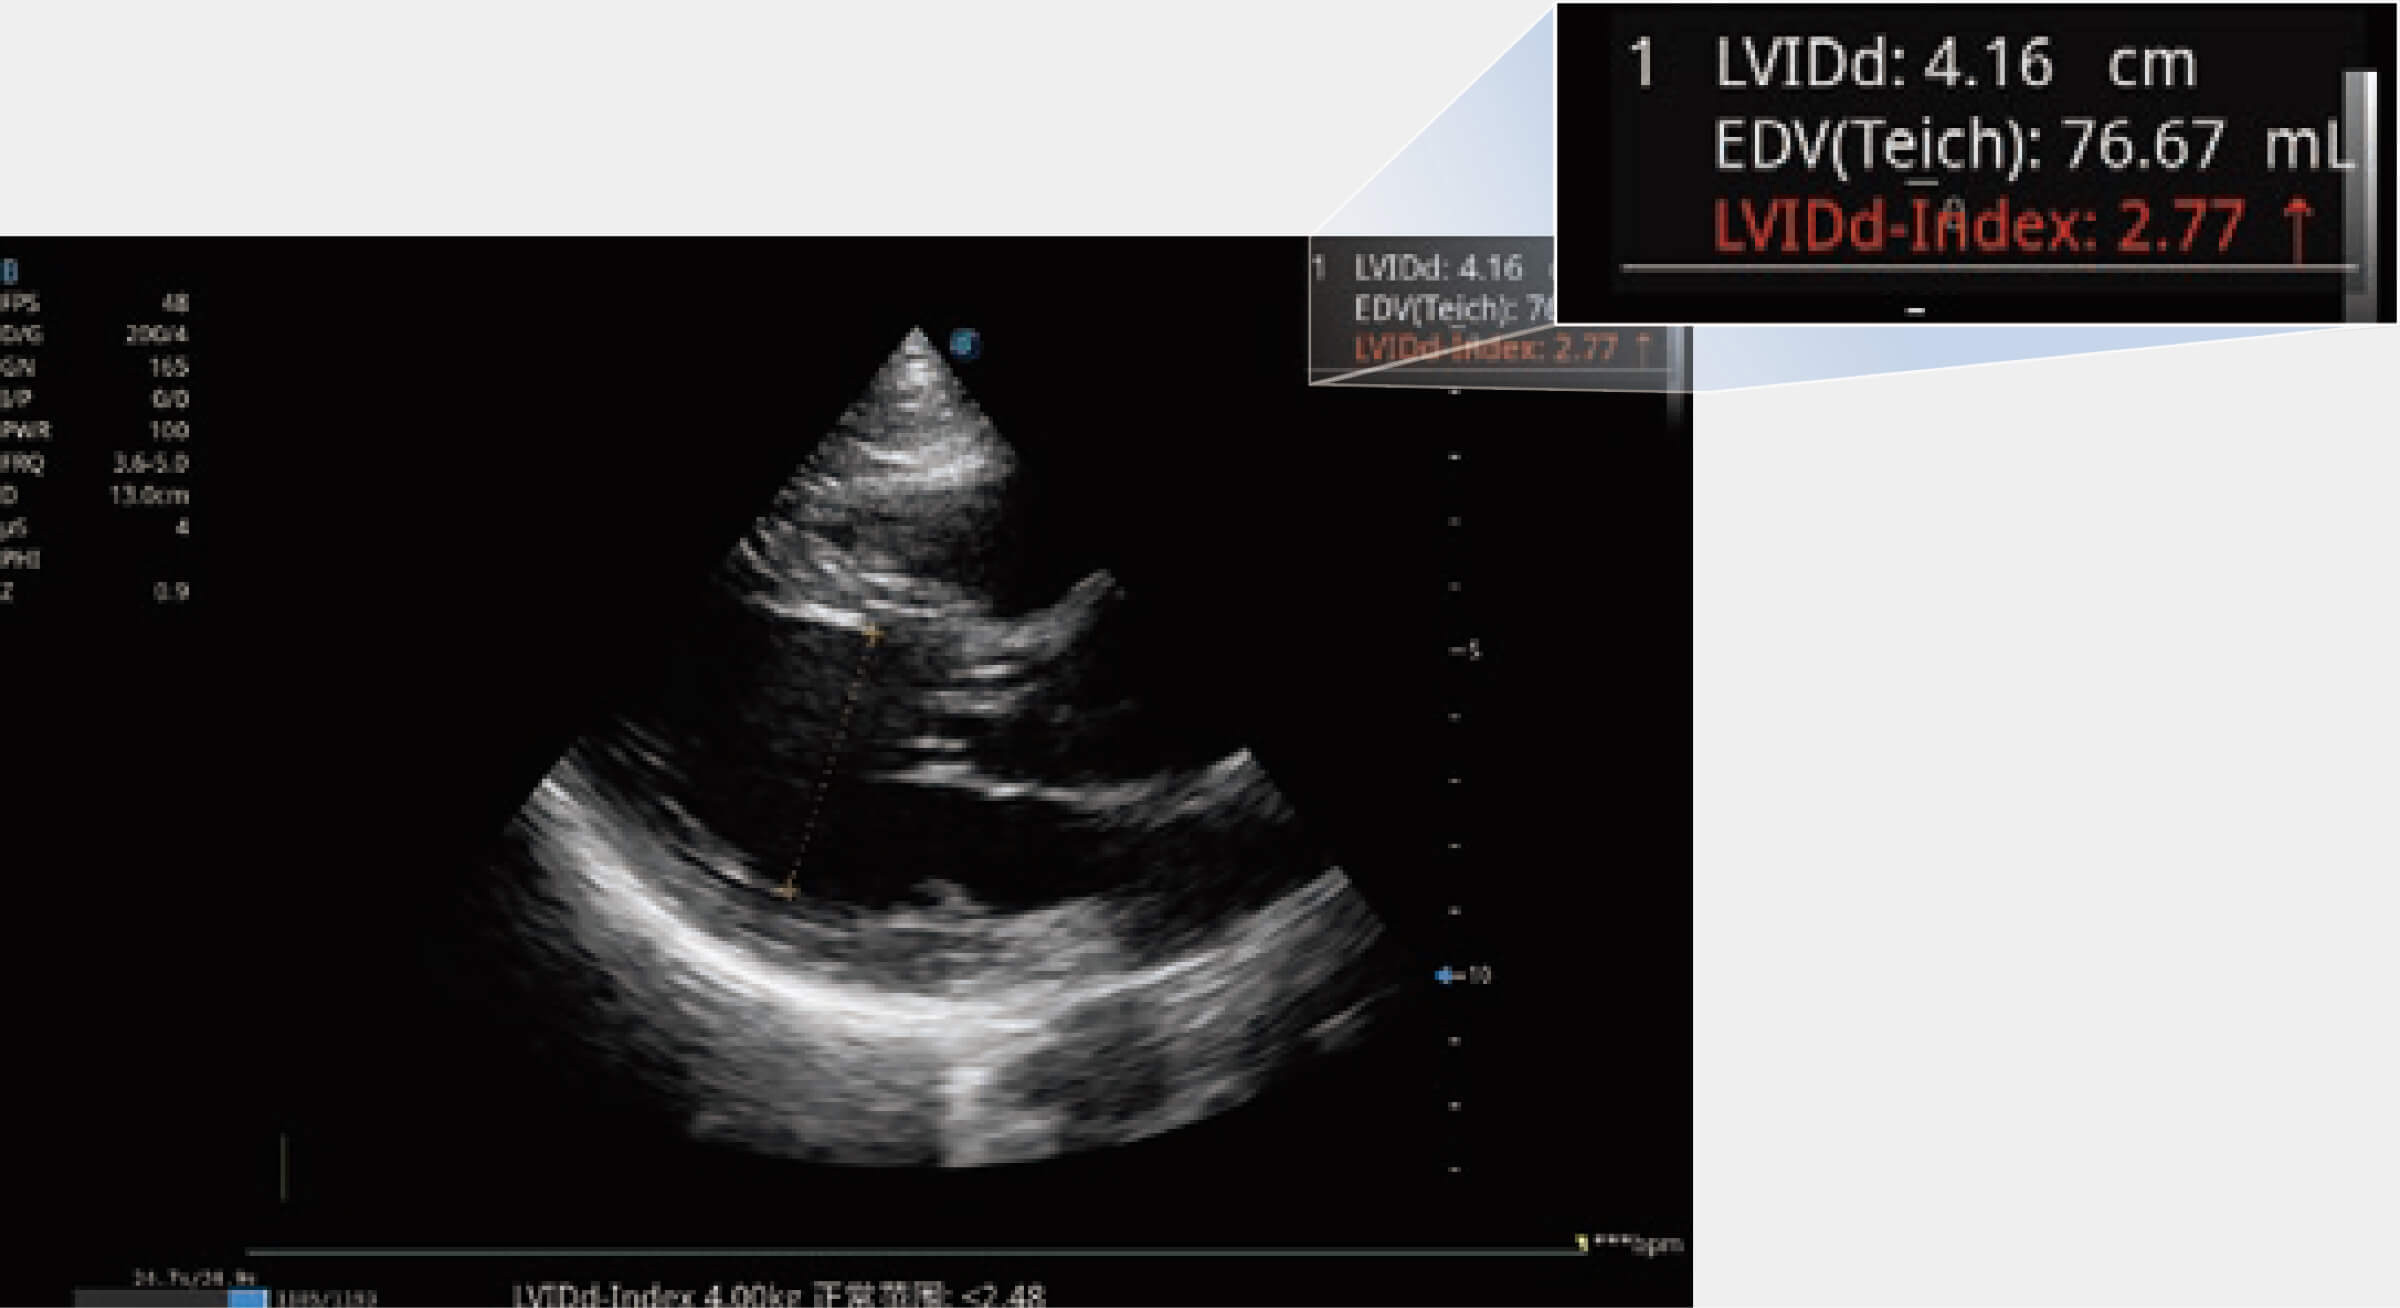

• Sono-Measure 測量值預(yù)警

當(dāng)心臟測量結(jié)果超出正常范圍時,可實時預(yù)警提示動物醫(yī)生,減少疾病漏診概率。

(犬)二腔心血流